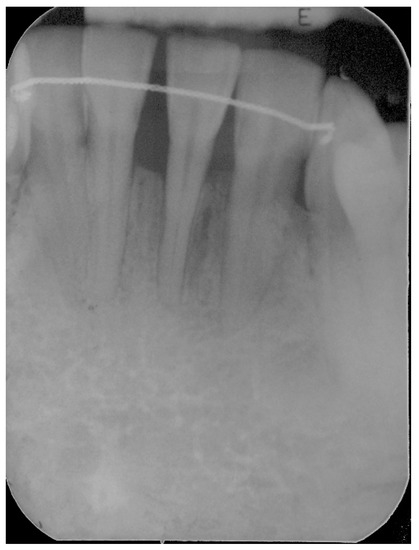

5. Materials and Methods

6. Results